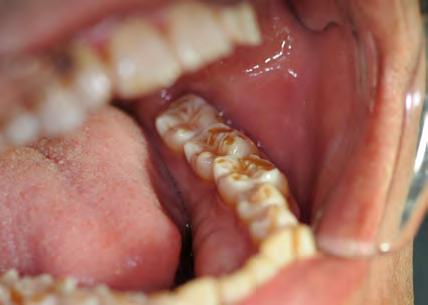

Figure 1. Example of characteristic Wickham striae and reticular pattern on buccal mucosa used to clinically diagnose OLL and OLP cases. Erythematous areas also seen. Figure 2. Frequency and percent of study patients using specific medications with color-coded drug classes.

The most common medication taken among subjects was metformin, comprising 24.6% (n=40). The most common phar macologic class was statin medications, at 36.4% (n=59); specifi cally, 15% (n=25) of patients took atorvastatin and 9% (n=15) took simvastatin. We also discovered that 17.9% (n=29) took proton-pump inhibitors and, interestingly, 16.7% (n=27) took le vothyroxine. These results are summarized in Figure 2 and Table 1.

Antihypertensives were the most common therapeutic class of medications among our subjects, at 49.4% (n = 80). As seen in Fig ures 2 and 3, when hypertension medications (color-coded green) are further subdivided into pharmacologic classes, beta blockers were the most associated with OLL/OLP, followed closely by angiotensinII-receptor blockers (ARBs) and calcium channel blockers (CCB). The thiazides are the next frequent type of hypertension medications taken by our OLL/OLP patient cohort. To our knowledge, our study is the first to further subtype the large and diverse class of hyperten sion medications associated with oral lichenoid lesions.